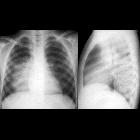

bakterielle Pneumonien Radiopaedia • CC-by-nc-sa 3.0 • de

Chest x-ray and CT are unable to differentiate bacterial pneumonia from non-bacterial pneumonia . There is also a large overlap of imaging features with non-pneumonic processes .

Bacterial pneumonia characteristically produces focal segmental (i.e. bronchopneumonia) or lobar pulmonary opacities (i.e. lobar pneumonia) . Expansion characterized by bulging fissures has typically been attributed to lobar pneumonia, in particular Klebsiella pneumonia, but there are many non-bacterial causes .